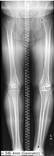

Leg length AI

Automatic measurement of leg lengths and angles. Limited generalizability.

N. Larson, C. Nguyen, BH. Do, et al.